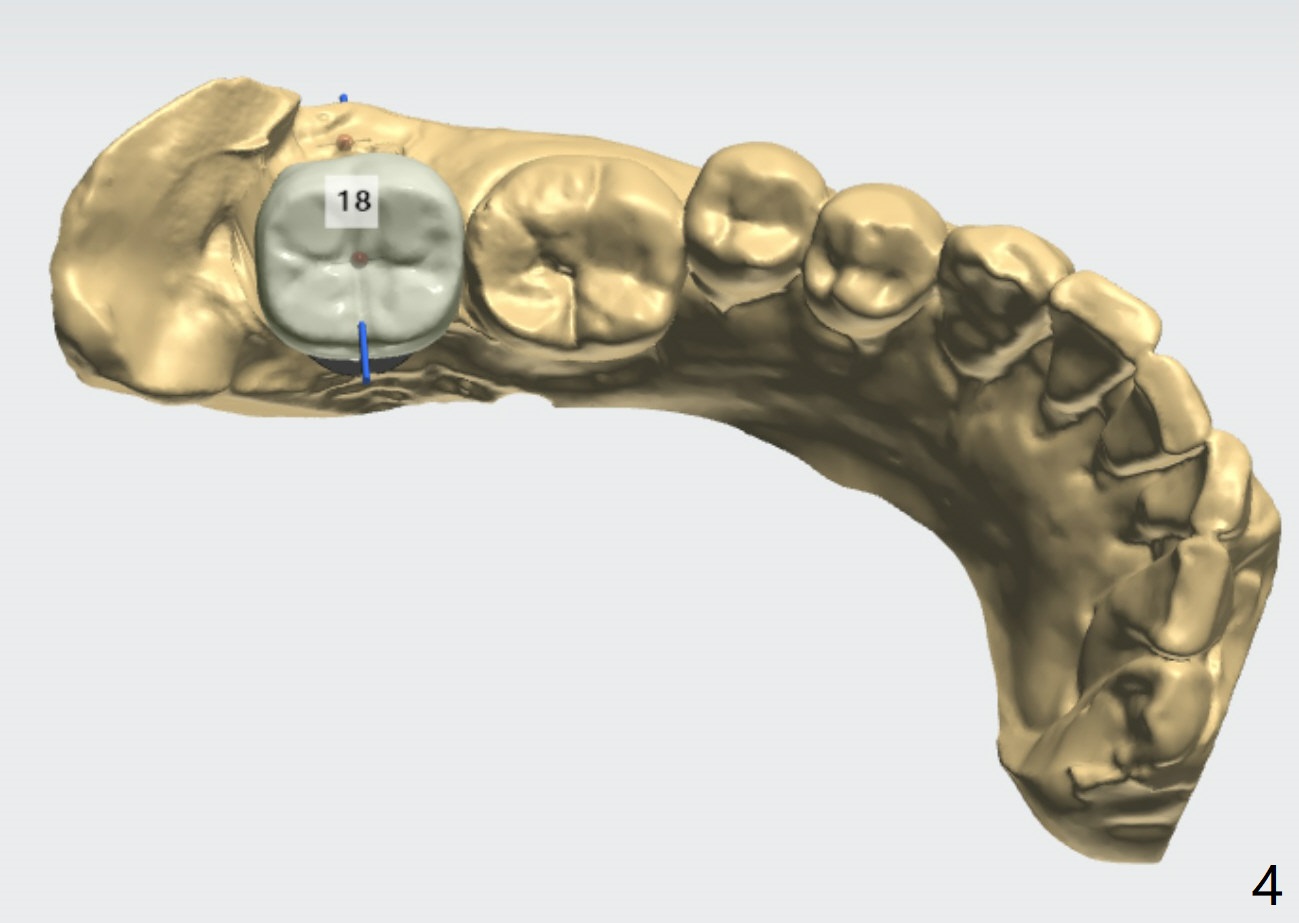

Bypass IAC/Angled Abutment